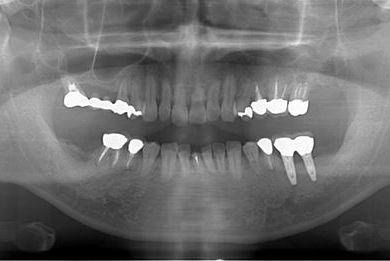

インプラントの症例写真 IMPLANT

インプラント治療+セラミック治療

| 治療内容 | インプラント2本、メタルボンドセラミッククラウン7本(メタルボンド用土台5本)、歯肉歯槽骨整形手術 | ||||||||||||||||||||||||||||||||

| 治療期間 | 11ヶ月 |